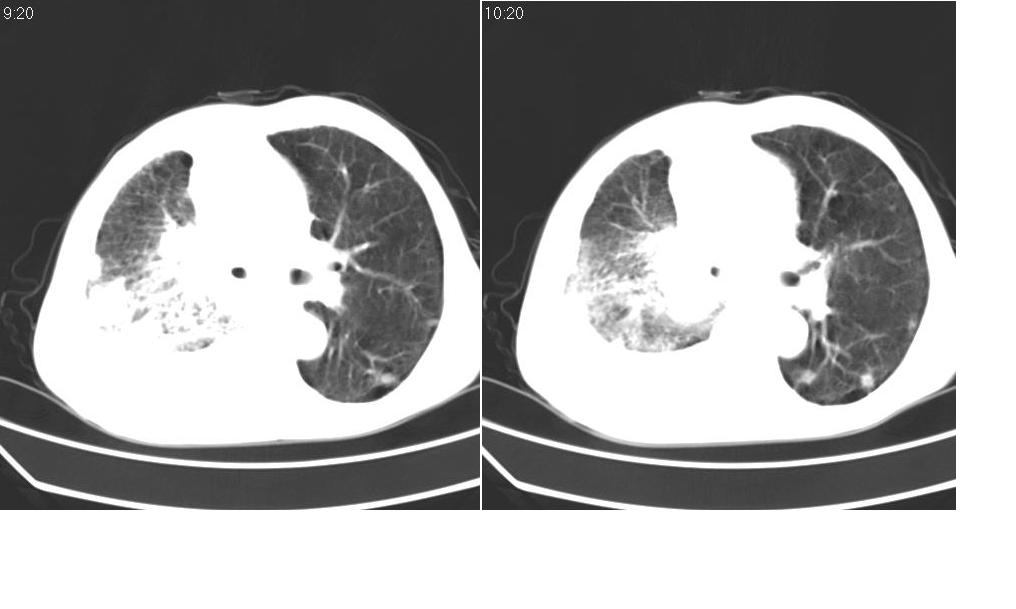

以下是引用zsl6918在2008-5-3 19:53:00的发言:[br]右肺中心型肺癌并纵隔淋巴结转移,胸膜转移,右肺癌性淋巴管炎。

以下是引用liuyue在2008-5-3 20:49:00的发言:[br]1.右侧中心型肺癌伴双肺转移瘤、纵隔淋巴结转移、右侧胸腔积液(侵及胸膜所致可能性大)。[br]2.右肺阻塞性肺炎,癌性淋巴管炎不除外。